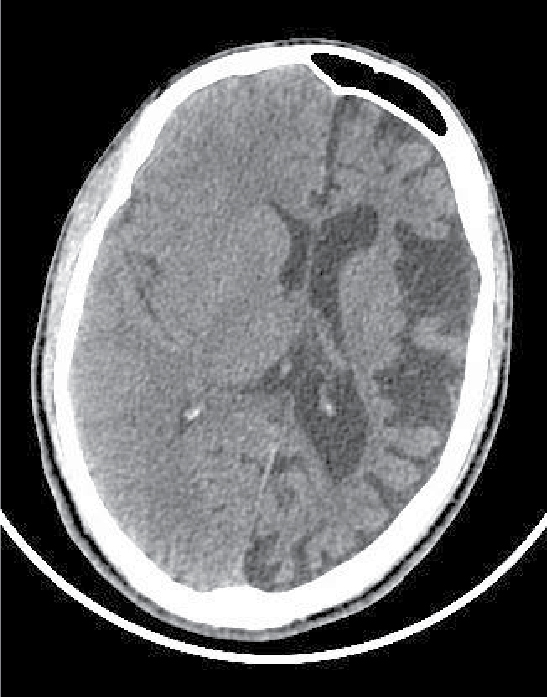

On examination, patient was conscious and oriented to time, place and person. There was extension at right elbow joint; pronated forearm and flexion at wrist joint (Fig. 1). Mental status examination revealed impaired calculation and Mini-Mental State Examination (MMSE) revealed a score of 24/30. On cranial nerve examination, patient had right upper motor neuron (UMN) type of facial nerve palsy. On motor examination, patient had gross wasting in right upper and lower limbs. Tone was markedly increased on right side of body with reduced power (3/5), brisk deep tendon reflexes and reduced sensation to touch, pain, temperature, vibration and proprioception. Plantar response was extensor on right side. Biochemistry was unremarkable. A provisional diagnosis of insidious onset gradually progressive sensorimotor hemiparesis with focal to generalized epilepsy with mental retardation was made. Noncontrast computed tomography (NCCT) head and magnetic resonance imaging (MRI) brain was performed, which revealed left cerebral hemiatrophy as evidenced by reduction in volume, prominence of cerebral sulci and dilation of left lateral ventricle. No other bony vault abnormality or prominence of frontal and mastoid air cells were seen (Figs. 2-4). Electroencephalogram (EEG) revealed epileptiform discharges in the form of sharp and slow wave complexes. Histopathology could not be done as attendants were not willing. Patient fulfilled the diagnostic criteria of RE (Table 1). He was treated with tablet phenytoin 100 mg TDS; tablet azathioprine 50 mg OD was started to halt progression of the disease. Patient had no episode of seizure thereafter. He was advised follow-up and repeat MRI brain was planned to check for any progression.

Figure 2. NCCT head showing left cerebral hemiatrophy as evidenced by reduction in volume, prominence of cerebral sulci and dilation of left lateral ventricle.